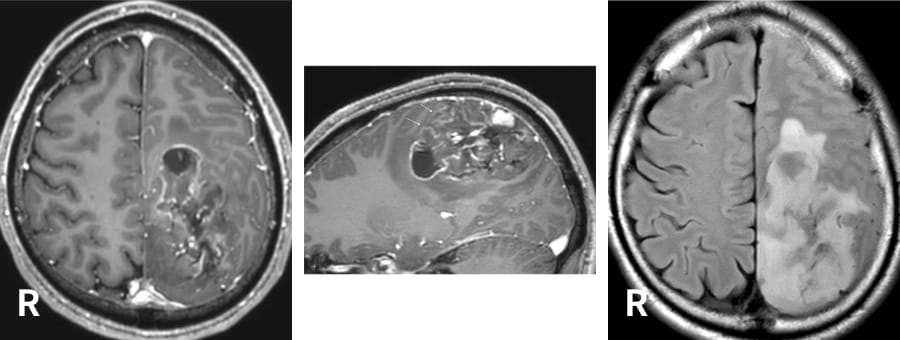

右下肢の感覚障害で発症された、左頭頂葉、長径約8 cmのグリオーマ(乏突起膠腫 Grade 3)。最も前方の嚢胞により中心溝が強く前方へ圧迫されていた。運動神経モニタリングの下で手術が行われ、ほぼ全摘出された。術前画像にて乏突起膠腫が疑われていたこともあり、摘出腔に抗がん剤ウエハースが留置された。

術前

術後